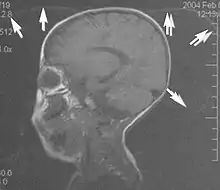

Metal artifacts occur at interfaces of tissues with different magnetic susceptibilities, which cause local magnetic fields to distort the external magnetic field. This distortion changes the precession frequency in the tissue leading to spatial mismapping of information. The degree of distortion depends on the type of metal (stainless steel having a greater distorting effect than titanium alloy), the type of interface (most striking effect at soft tissue-metal interfaces), pulse sequence and imaging parameters. Metal artifacts are caused by external ferromagnetics such as cobalt containing make-up, internal ferromagnetics such as surgical clips, spinal hardware and other orthopaedic devices, and in some cases, metallic objects swallowed by people with pica.[3] Manifestation of these artifacts is variable, including total signal loss, peripheral high signal and image distortion (Figs 3 and 4).[1] Reduction of these artifacts can be attempted by orientating the long axis of an implant or device parallel to the long axis of the external magnetic field, possible with mobile extremity imaging and an open magnet. Further methods used are choosing the appropriate frequency encoding direction, since metal artifacts are most pronounced in this direction, using smaller voxel sizes, fast imaging sequences, increased readout bandwidth and avoiding gradient-echo imaging when metal is present. A technique called MARS (metal artifact reduction sequence) applies an additional gradient, along the slice select gradient at the time the frequency encoding gradient is applied. ==Signal processing dependent artifacts== The ways in which the data are sampled, processed and mapped out on the image matrix manifest these artifacts.[1]